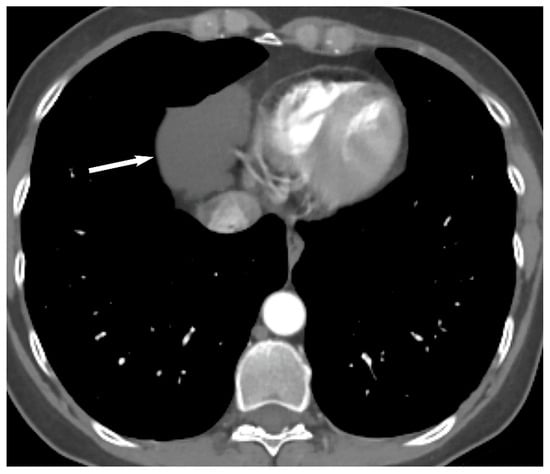

Visceral (Middle) Compartment

8. Cystic Lesions

9. Hypervascular Lesions

10. Esophageal Lesions